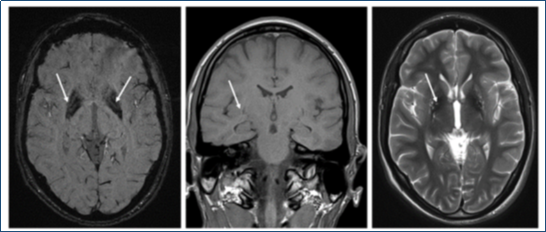

Неврологический статус: сознание ясное, контактна, ориентирована правильно. Менингиальных симтопомов нет, лицо симметрично, умеренная гипомимия. Слух (при ориентировочной оценке) сохранен. Дистония в левой кисти в виде тыльного переразгибания пальцев кисти и последующего сжатия в кулак, стриарная стопа слева. Походка на расширенной базе, с подволакиванием левой ноги и дистонией в левой руке в виде отведения в сторону сгибания кисти, ахейрокинез справа. При биомикроскопии отмечается наличие колец Кайзера-Флейшера. Оценка когнитивных функций по шкале МоСА отмечается 22/30 баллов. В ЭЭГ регистрируется сохранный корковый ритм, тета-ритм слабо выражен. Стол — 5а. На рисунке 8 изображено МРТ пациентки П.

Рис. 8. МРТ пациентки П. Симметричное поражение бледных шаров (отложение меди), уменьшение в объеме лентикулярных ядер